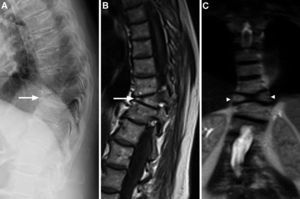

Radiografía lateral de columna dorsal mostrando un aparente aplastamiento vertebral cuneiforme anterior de D10 (A, flecha). La RM mostraba en los cortes sagitales de la secuencia potenciada en T1 un acuñamiento anterior similar al observado en la radiografía (B, flecha), pero en los cortes coronales se evidenció que en realidad correspondía a un defecto de fusión del cuerpo vertebral, que originaba la presencia de 2 hemivértebras, la derecha ligeramente menor que la izquierda, con la apariencia típica de «vértebra en mariposa» (C, cabezas de flechas).

La vértebra en mariposa (también conocida como hendidura sagital vertebral, raquisquisis anterior, somatosquisis, o espina bífida anterior1) es una malformación congénita rara producida por el fallo de la fusión de los núcleos de condrificación laterales de la vértebra en desarrollo2,3, secundario a una regresión embriológica incompleta de la notocorda que origina un surco sagital en forma de embudo dentro del cuerpo vertebral, a través del cual se conectan los discos vertebrales adyacentes4. Este defecto ocurre entre la 3.ª a 6.ª semana de gestación2,3 y se localiza con mayor frecuencia a nivel lumbar5–7. Se asocia a otras alteraciones congénitas como la hipo/aplasia mülleriana y los síndromes de Jarcho-Levin, Pfeiffer, Crouzon, Alagille y Kallmann, aunque también puede ocurrir de forma aislada1,2,7,8. Los pacientes habitualmente son asintomáticos y esta malformación suele detectarse de forma incidental, pero puede alterar la biomecánica de la columna causando dolor lumbar atípico o aumentando la posibilidad de herniación discal5–7. En la radiografía lateral muestra una morfología trapezoidal o cuneiforme anterior, por lo que puede confundirse con un aplastamiento vertebral osteoporótico u otras fracturas vertebrales patológicas, incluyendo las traumáticas, infecciosas o metástasicas1,2,7,9. El acuñamiento es causado por hipo/aplasia anterior debido a un déficit congénito de la vascularización3,9. En la radiografía anteroposterior se detecta fácilmente debido a que la vértebra se divide en 2 hemivértebras (habitualmente simétricas, pero pueden ser de tamaño distinto condicionando escoliosis), que lucen como las alas de una mariposa1,2,4, pero esta radiografía no estuvo disponible en nuestro caso. La TC y la RM se recomiendan en casos dudosos o para excluir otras anomalías congénitas asociadas tales como barras vertebrales, vértebras lumbares supernumerarias, espina bífida, diastematomielia o cifoescoliosis6. Recientemente, se ha descrito el uso de la ultrasonografía fetal tridimensional para el diagnóstico prenatal de la vértebra en mariposa10. En conclusión, aunque la vértebra en mariposa es infrecuente, debería tenerse en cuenta en el diagnóstico diferencial del aplastamiento vertebral osteoporótico.